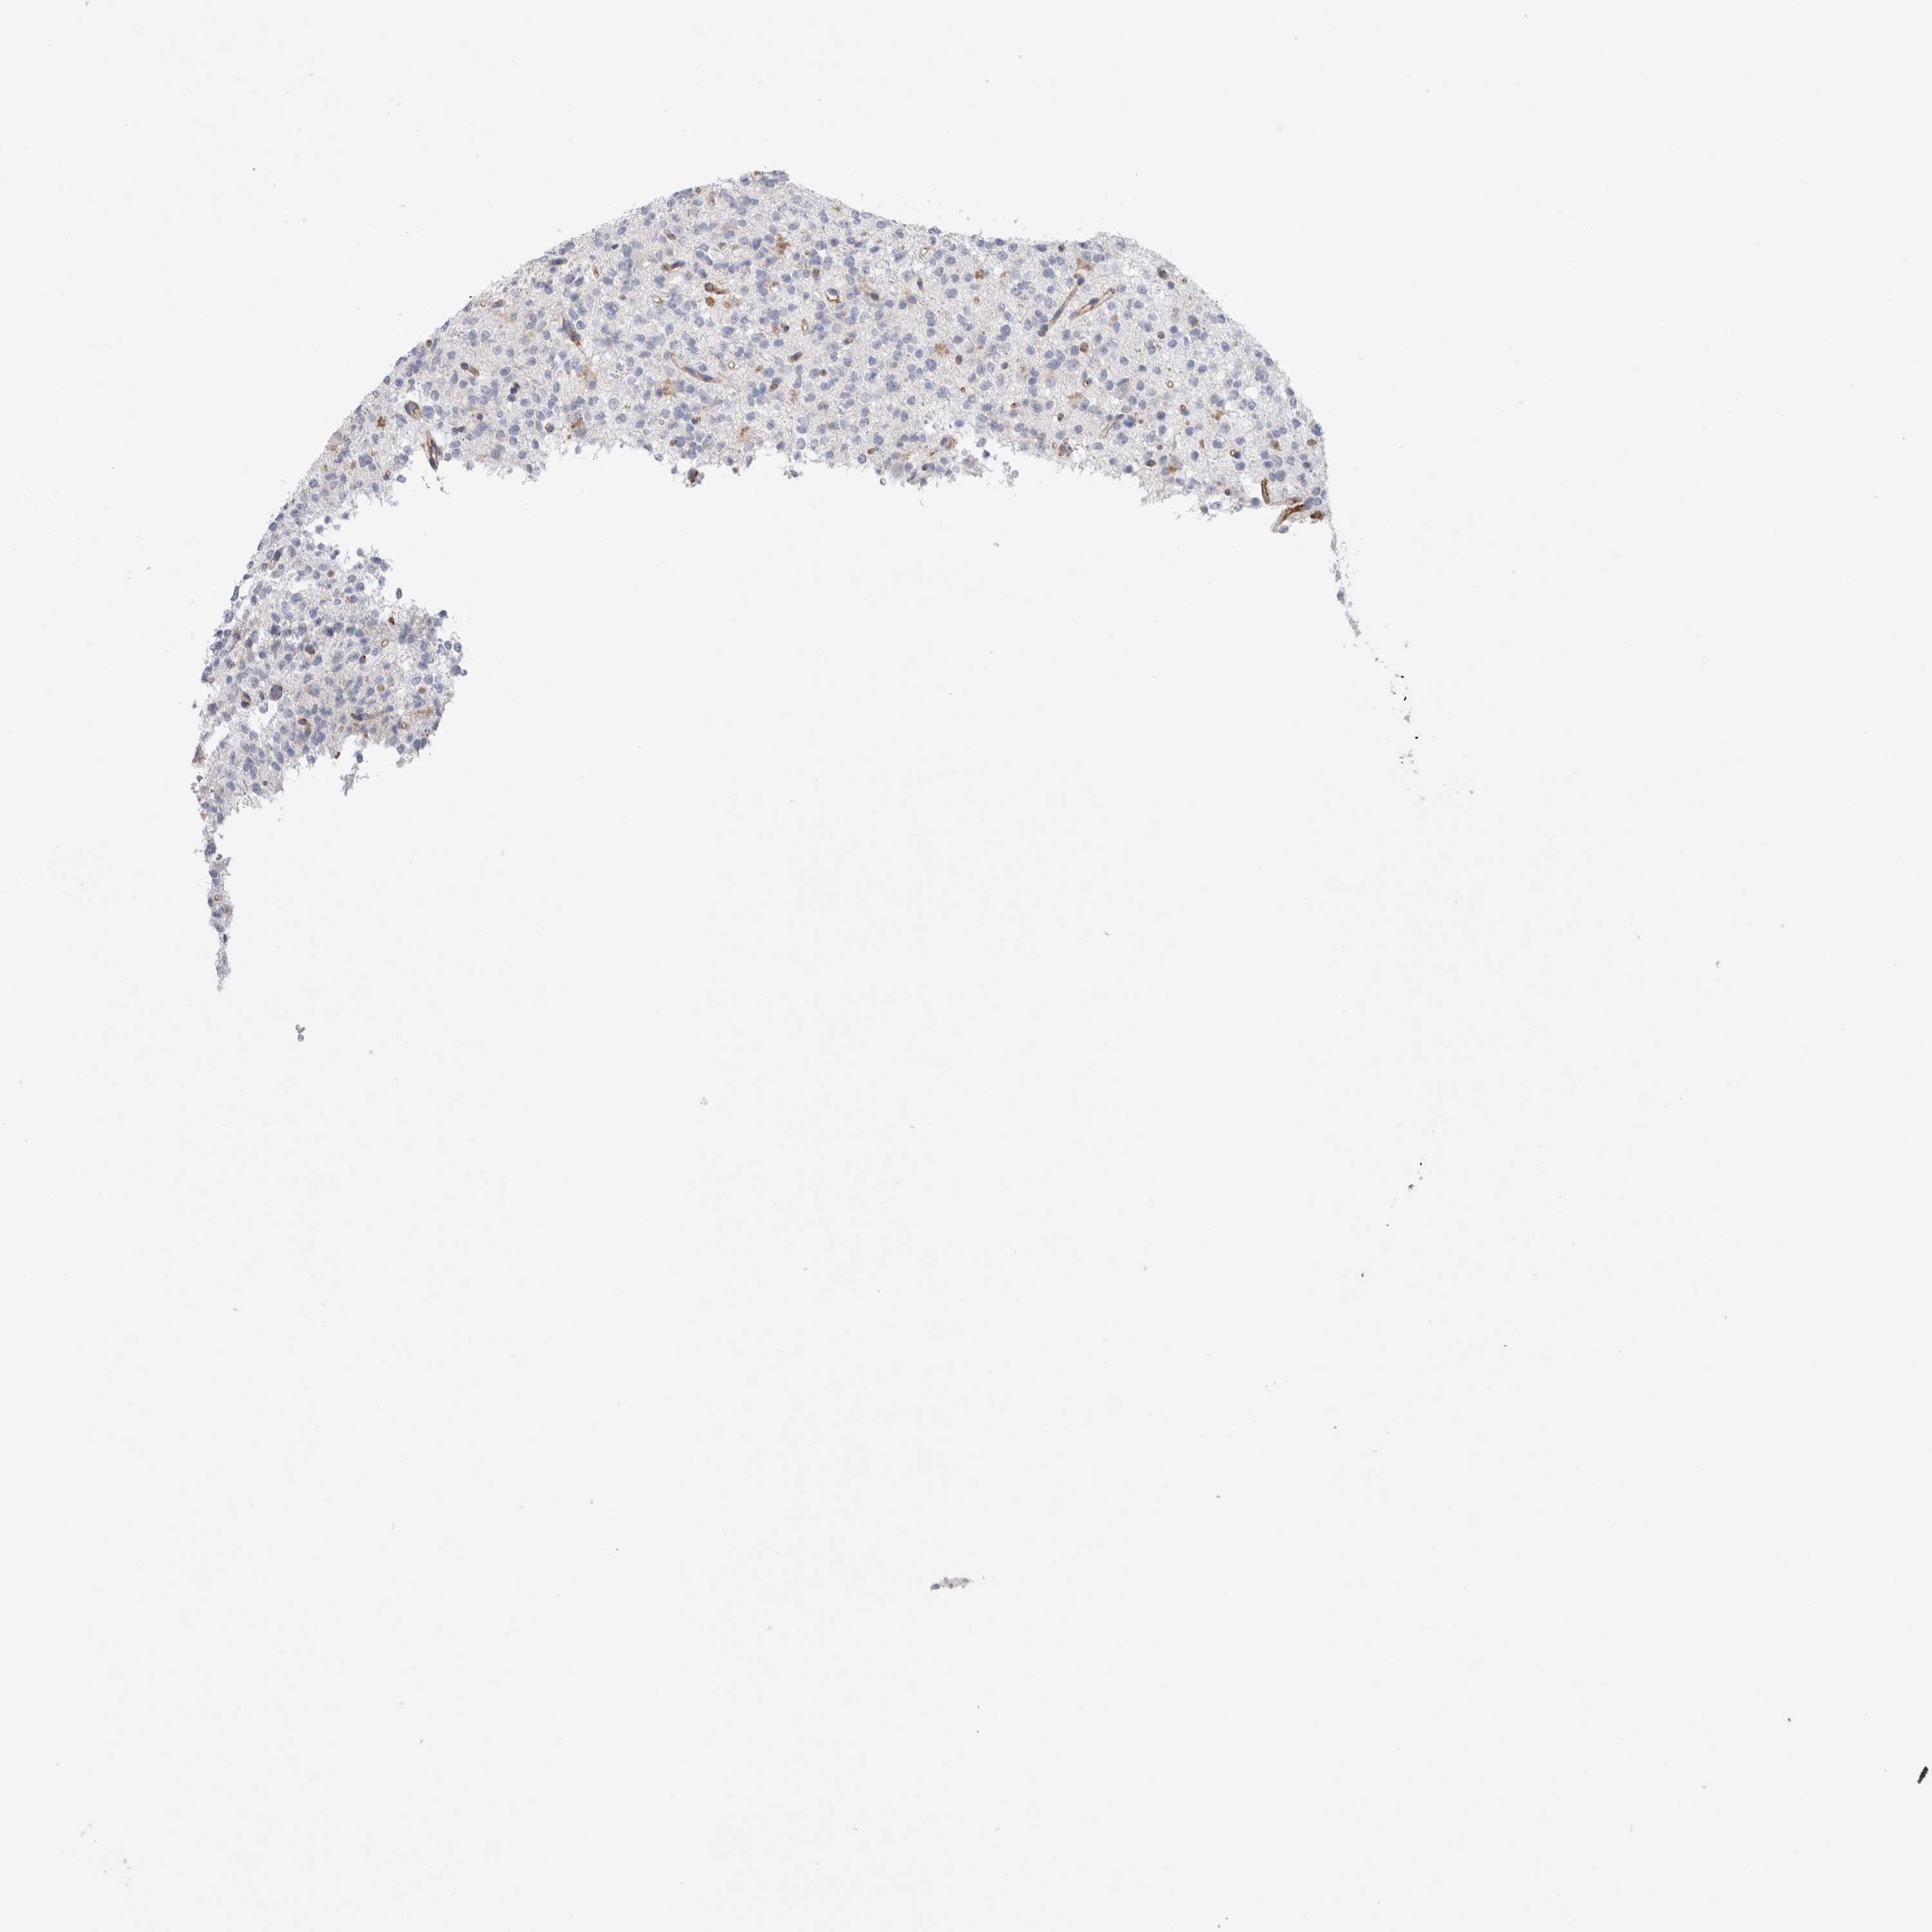

GLIOMA - Protein expressioni

A mouse-over function shows sample information and annotation data. Click on an image to view it in a full screen mode. Samples can be filtered based on level of antibody staining by selecting one or several of the following categories: high, medium, low and not detected. The assay and annotation is described here.

Note that samples used for immunohistochemistry by the Human Protein Atlas do not correspond to samples in the TCGA dataset.

Antibody stainingi

Antibody staining in the annotated cell types in the current human tissue is reported as not detected, low, medium, or high, based on conventional immunohistochemistry profiling in selected tissues. This score is based on the combination of the staining intensity and fraction of stained cells.

Each image is clickable and will lead to virtual microscopy that enables deeper exploration of all samples and also displays staining intensity scores, fraction scores and subcellular localization as well as patient and tissue information for each sample.

Antibody HPA014166

Antibody HPA025240

Staining

High

Medium

Low

Not detected

Intensity

Strong

Moderate

Weak

Negative

Quantity

>75%

75%-25%

<25%

None

Location

Nuclear

Cytoplasmic/membranous

Cytoplasmic/membranous,nuclear

Glioma, malignant, High grade

Glioma, malignant, Low grade